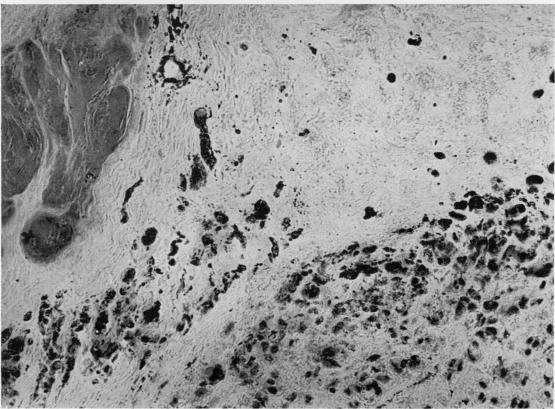

ULTRAMICROSCOPIC STRUCTURE OF THE RHEUMATOID NODULE.

Ann Rheum Dis. 1964 Sep;23(5):345-63. doi: 10.1136/ard.23.5.345.